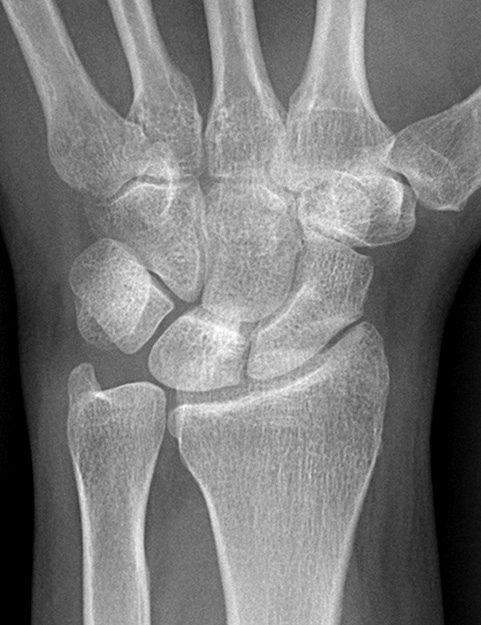

Diagnosis? Etiology?

Keinbochs

Diagnosis? Classification

Keinboch’s - Litchman Classification

Imaging to help define collapse of lunate